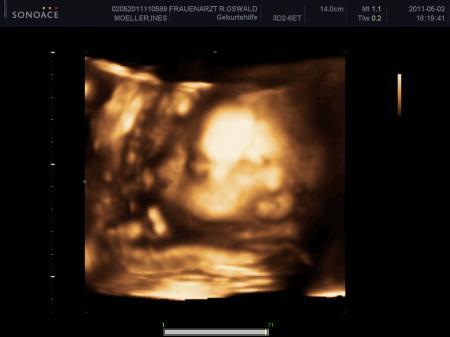

Am Fruchtwasser trinken

Bild zu